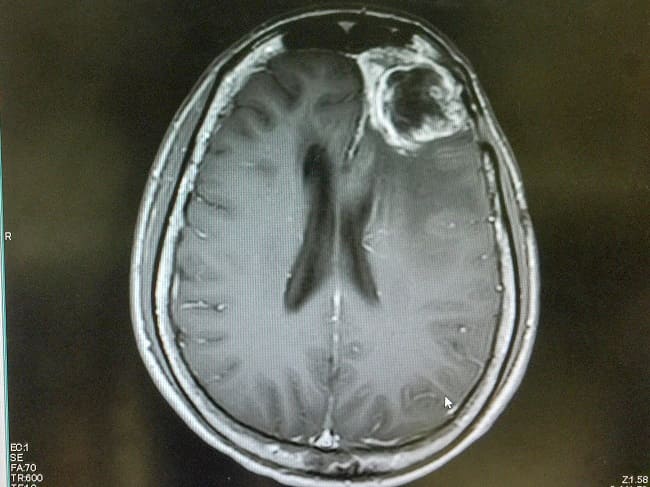

Gejala klinis glioblastoma sangat bervariasi, ditentukan oleh ukuran tumor, lokasi tumor, dan struktur anatomi otak yang terlibat. Pasien sering menunjukkan gejala tekanan tinggi intrakranial, seperti nyeri kepala hebat dan defisit neurologis baik fokal maupun gangguan kognitif. CT scan kepala atau MRI otak merupakan pemeriksaan radiologis diagnostik untuk glioblastoma.[1,3]